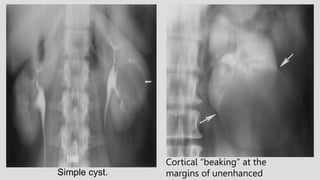

Simple cyst.

Cortical “beaking” at the

margins of unenhanced